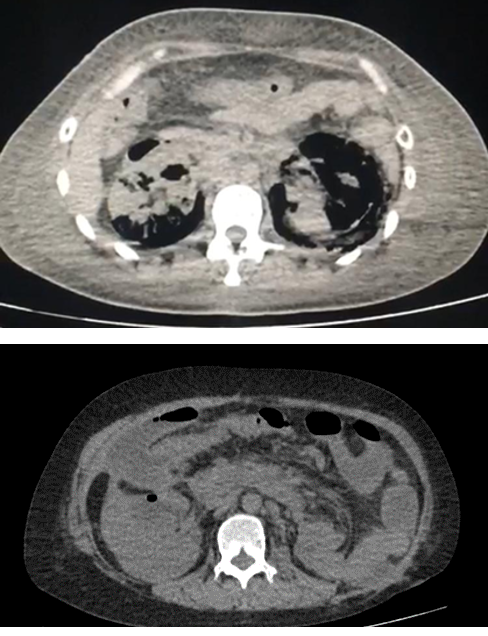

| 4. Gas en riñón único o enfermedad bilateral. (Imagen 4) |

La tomografía computada es el procedimiento de diagnóstico por imagen de elección para definir la extensión del proceso enfisematoso y puede orientarnos en la elección del tratamiento. La ausencia de líquido en las imágenes tomográficas o la presencia de patrones gaseosos estriados o jaspeados con acumulación de gas en burbujas o con tabiques, parece asociarse con una destrucción rápida del parénquima renal y una tasa de mortalidad de entre 50 y 60%.1-3 La presencia de líquido en el espacio renal o perirrenal y de gas en burbujas o entre tabiques o de gas en el sistema colector, y la ausencia de patrones estriados o jaspeados se asocia con una tasa de mortalidad menor del 20%.1- 3 Se identifican obstrucciones en alrededor del 25% de los casos. Algunos autores consideran necesaria la realización de un gammagrama renal.2,20